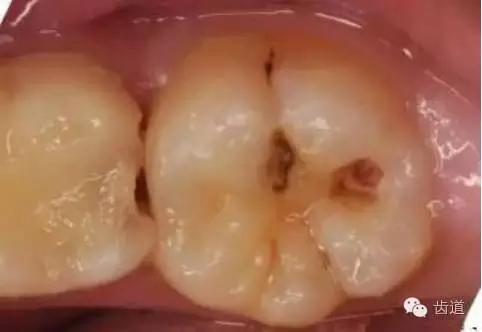

齲病的治療原則

1、淺齲:指釉質(zhì)齲,發(fā)生于牙頸部時為牙骨質(zhì)齲和(或)牙本質(zhì)齲。

2、中齲:牙本質(zhì)淺層齲。

3、深齲:牙本質(zhì)深層齲

4、可疑齲:指窩溝處較深,色黑,有患齲傾向,未形成典型淺齲。

2、淺齲:充填術(shù)。

3、中齲:墊底充填或直接充填。

4、深齲:如洞底變色軟齲去凈且牙髓狀況正常,行OC安撫術(shù)、間接蓋髓、墊底充填。如軟齲不能去凈或牙髓充血,行根管治療術(shù)+全冠修復(fù)